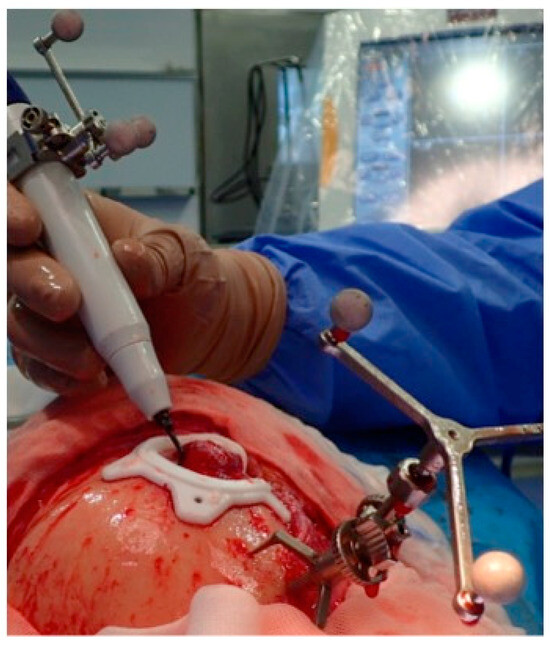

2.3.3. Surgical Navigation

| 1 | 53/F | L/25 mm | Y | 4 mo | Dystopia | N | CT, MRI | Supraorbital rim, orbital roof | Intraosseous venous malformation | - | Resection + reconstruction | Y | Y | 1st, 2nd, 3rd | Coronal | Y | Piezoelectric device | N | PEEK prosthesis | 7 y/N |

| 2 | 54/F | R/33 mm | Y | 9 y | N | Y | CT, MRI | Frontal bone, orbital roof | Intraosseous venous malformation | - | Resection + reconstruction | Y | Y | 1st, 2nd, 3rd | Coronal | Y | Piezoelectric device | N | PEEK prosthesis | 6 y/N |

| 3 | 36/F | L/19 mm | Y | 6 mo | N | N | CT, MRI | Zygoma | Arteriovenous malformation | - | Resection + reconstruction | Y | Y | 1st, 2nd, 3rd | Transconjunctival + blepharoplasty + maxillary vestibular | Y | Piezoelectric device | N | PEEK prosthesis | 5 y/N |

| 4 | 47/M | L/30 mm | N | 2 y | N | N | CT | Zygoma | Intraosseous venous malformation | - | Resection + reconstruction | Y | Y | 1st, 2nd, 3rd | Transconjunctival + lateral canthotomy + maxillary vestibular | Y | Piezoelectric device | N | PEEK prosthesis | 6 y/N |